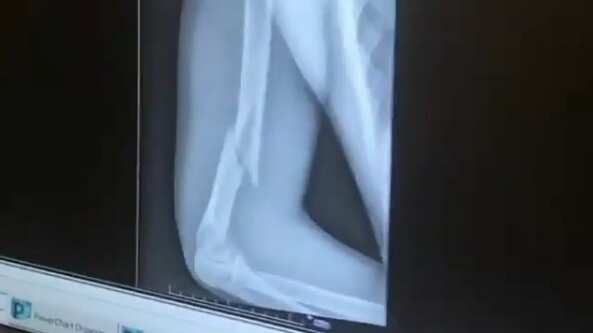

Según un video que publicó Fernán Vélez, conocido como “El Nalgorazzi”, se observa la grave fractura que tuvo el artista en su brazo derecho.

En la misma se ve que el intérprete de “Me niegas” tiene un hueso roto.